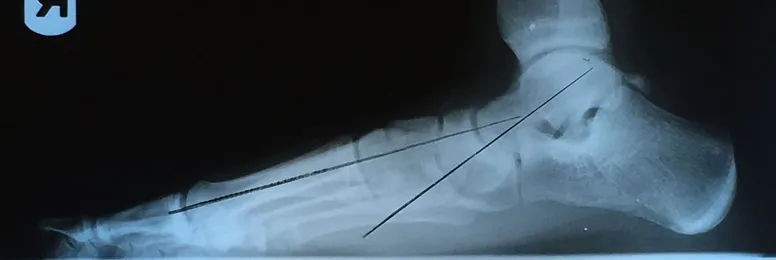

Pre and Postop X-rays Subtalar Joint Implant (Below)

Patient JD